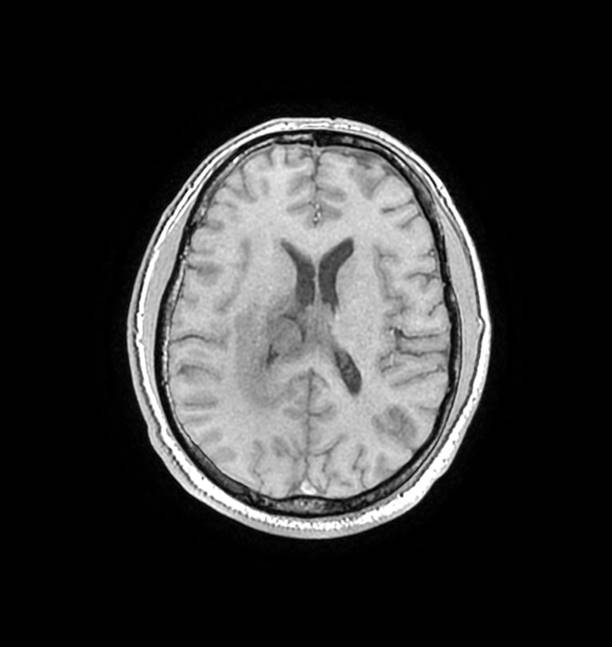

磁共振影像圖

圖1

MR診斷:右側(cè)側(cè)腦室三角區(qū)及側(cè)腦室旁占位,考慮惡性腫瘤可能,間變型腦膜瘤?轉(zhuǎn)移瘤?